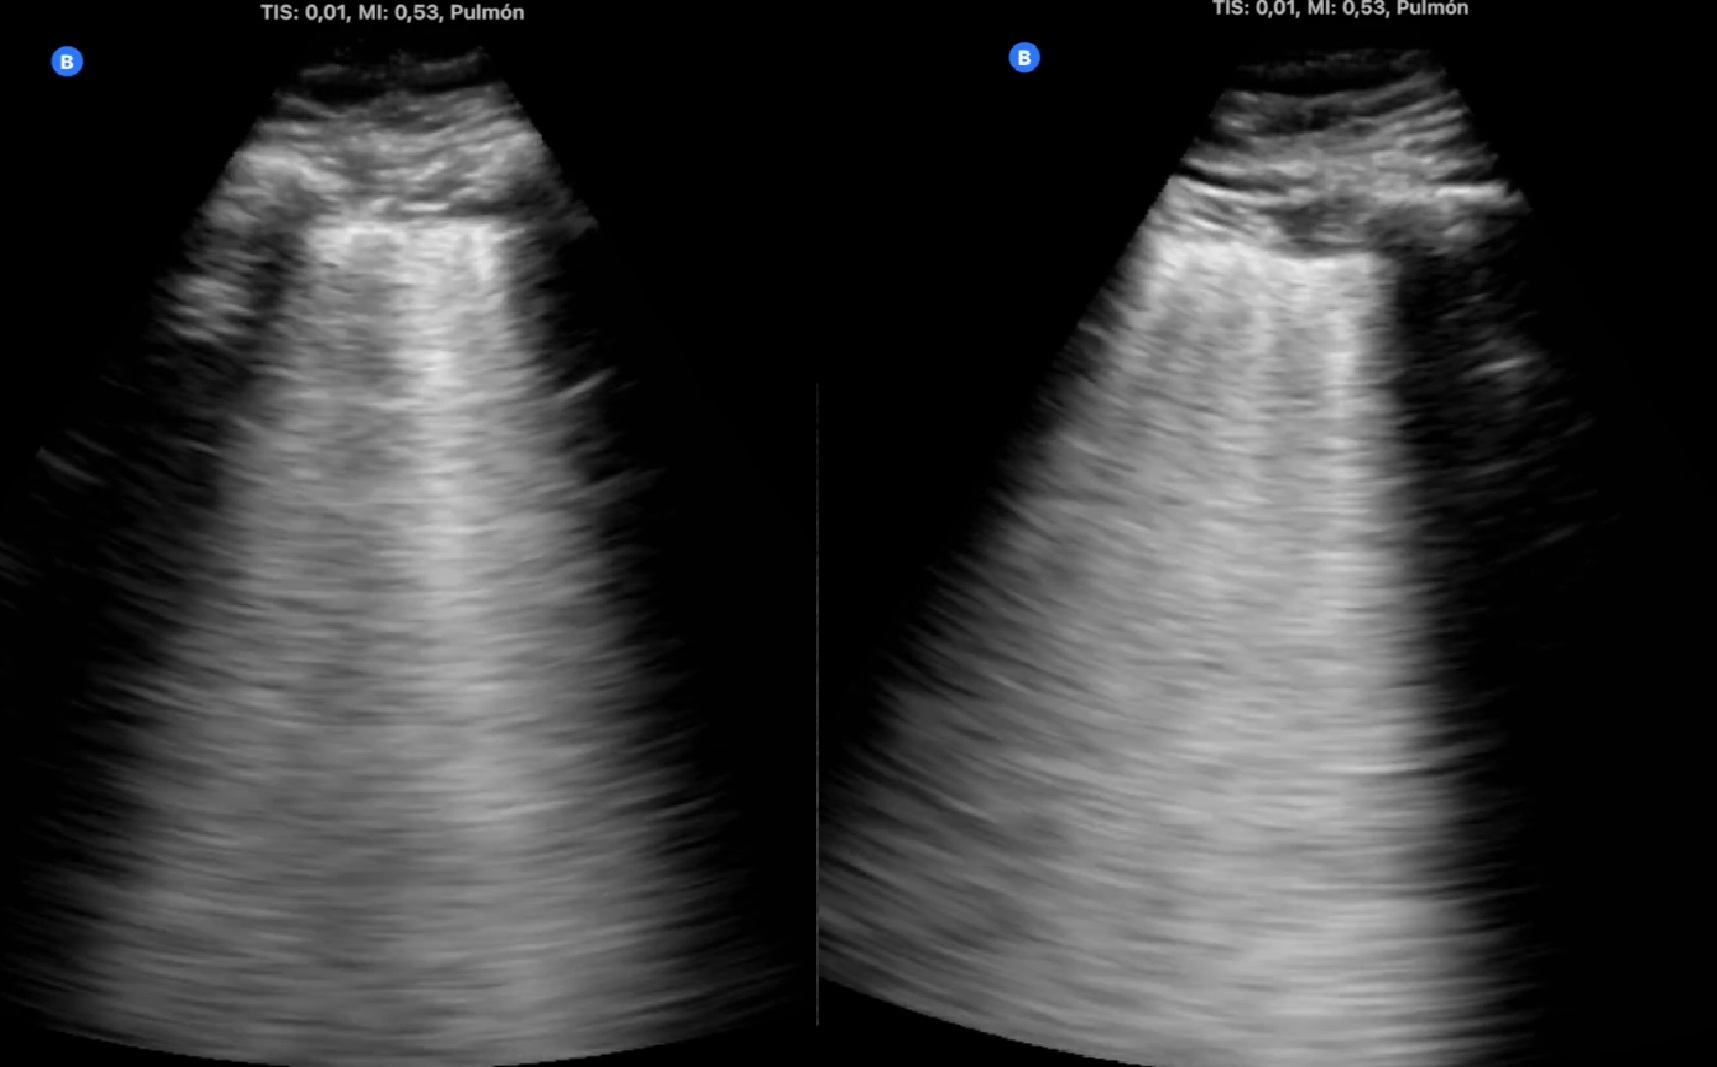

Se hace ecografía pulmonar en ambos casos.

Descripción de los hallazgos ecográficos y las imágenes más relevantes para la resolución del caso

Evolución y seguimiento

Desaparición de síntomas en los primeros dos días. Seguimiento ecográfico que muestra la desaparición de la neumonía a los 15 días en el primer caso y reducción paulatina del tamaño de la lesión en el segundo.